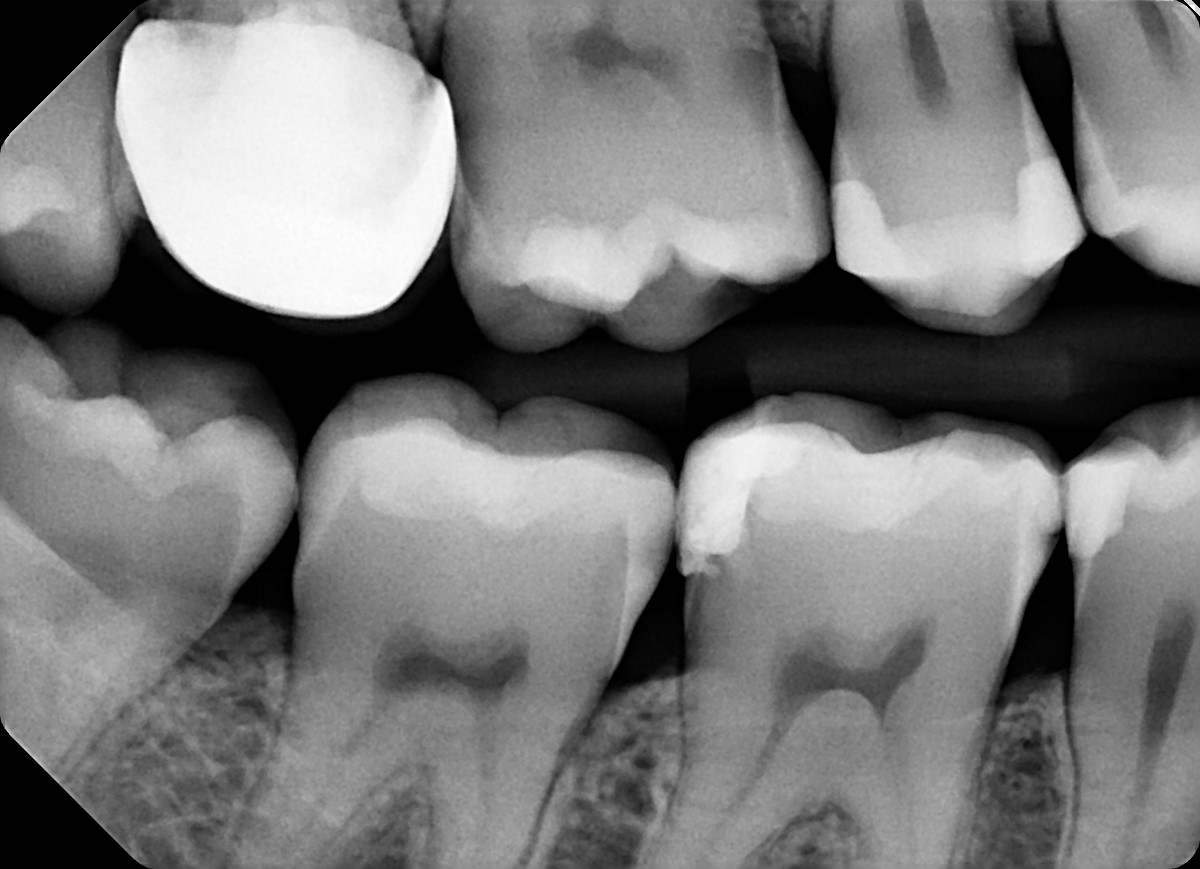

4. In the X ray bellow for which jaw periodontal bone loss is evident?